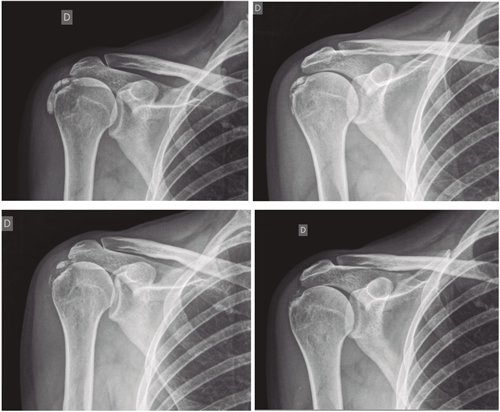

El número promedio de sesiones en nuestra serie fue de 20. El criterio para continuar o suspender el tratamiento fue la evolución radiológica y clínica (Figuras 4 y 5). Las intervenciones se realizaron hasta un máximo de 40 sesiones. Perrón trató a sus pacientes por 9 sesiones (3 sesiones semanales por 3 semanas) (14). Leduc trató con 10 sesiones (3 por semana las dos primeras semanas; y luego una semanal por 4 semanas) (15). Rioja-Toro trató a sus pacientes por 40 sesiones (5 veces por semana) y los evaluó a las 20 y a las 40 sesiones (3). Chico-Álvarez trató a sus pacientes entre 15 y 30 sesiones dependiendo de la evolución radiológica (5 veces por semana) (1).

Fig. 4. Paciente mujer de 47 años con tendinitis calcificante de supraespinoso derecho, de tipo formativa, quien tras 30 sesiones de iontoforesis disminuyó el dolor medido por EVA de 6/10 a 3/10 y la calcificación de 38 mm a 8 mm (valoraciones al inicio, a las 10, a las 20 y a las 30 sesiones, respectivamente).

El estudio que se ha realizado es cuasiexperimental tipo antes-después, e incluyó a 138 pacientes. Perrón (14) realizó un estudio experimental randomizado (n = 11 grupo experimental; n = 10 grupo control), lo mismo que Leduc (15) (n = 17 grupo experimental; n = 10 grupo control). Rioja-Toro (3) realizó un estudio experimental tipo antes-después a 34 pacientes (n = 34). Chico-Álvarez (1) realizó un estudio experimental randomizado (n = 25 grupo experimental 1; n = 25 grupo experimental 2; n = 25 grupo experimental 3).

Fig. 5. Paciente mujer de 44 años, con tendinitis calcificante de supraespinoso izquierdo, de tipo resortivo, quien tras 20 sesiones de iontoforesis disminuyó el dolor medido por EVA de 10/10 a 4/10, y la calcificación de 22 mm a 0 mm (desaparición completa).